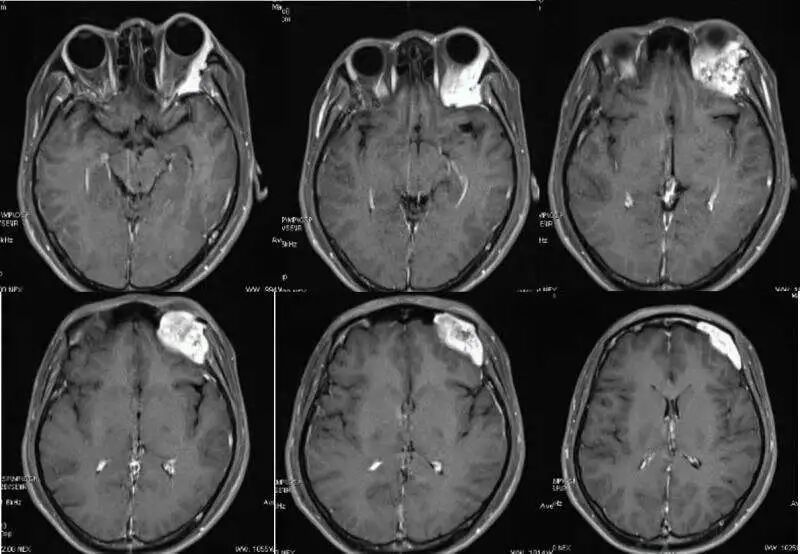

关于颅骨血管瘤

颌骨中央性血管瘤是一种少见的以异常血管增殖为特征的先天性良性肿瘤。源于血管内皮细胞的异常增生,是血管畸形或类瘤肿块,并非真性肿瘤。占颌面部软组织血管瘤的3%~4.1%,多见于10~19岁年龄段,约2/3发生于下颌骨,男∶女比例约为1∶2。早期无明显症状和体征,后期可出现牙齿松动移位、咬合错乱、牙龈反复出血(夜间加重)、面部膨隆、局部麻木或疼痛。

颌骨中央性血管瘤的确诊主要依靠病理学诊断,若血管瘤一旦破裂,容易引起大出血,故临床上严禁活检。颌骨中央性血管瘤的危险性在于因外伤或拔牙导致大出血,严重时引起失血性休克,甚至死亡。故紧急止血是应对该病导致大出血的关键。急救处理主要有填塞、压迫止血;颈外动脉结扎;输血补充血容量,纠正休克;必要时行气管切开,术后再行填塞、压迫止血;急诊行颌骨及肿瘤切除术等。